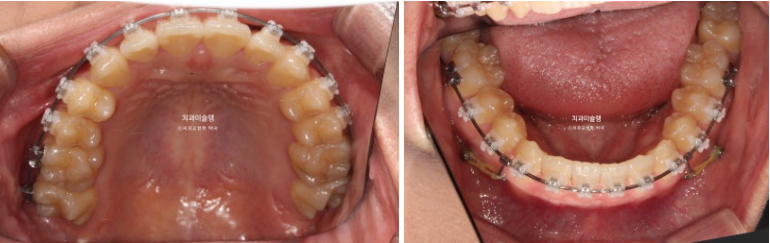

23.09

어릴때 교정을 했었고 아래턱이 자라 앞니가 거꾸로 물리게 되었습니다.

측방치군, 즉 송곳니와 작은어금니에 개방교합이 보입니다.

아래 앞니가 위 앞니보다 앞에 물려 거꾸로 물림, 반대교합이 보입니다.

아래 매복 사랑니가 있어서 사랑니를 발치하고 사랑니 공간으로 아래 전체치열을 뒤로 미는 교정이 필요합니다.

기존에 붙어있던 유지장치 제거 후 클리피씨 교정을 하기로 합니다.